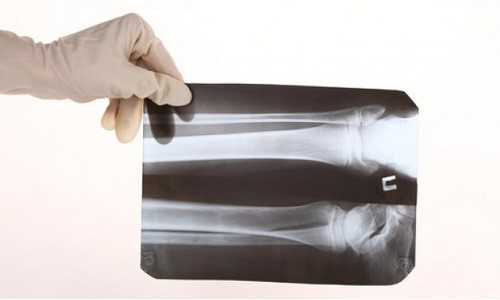

Снимки предплечья в двух взаимно перпендикулярных проекциях чаще всего выполняют при травмах.

Укладка больного для выполнения снимка. Больной сидит боком к столу.

Рука отведена, расположена на столе или на подставках. Кассета размером 18X24 или 24X30 см, наполовину перекрытая листом просвинцованной резины, располагается под задней поверхностью предплечья таким образом, чтобы на снимке были захвачены проксимальные и дистальные концы костей. Пучок рентгеновского излучения направляют на середину предплечья перпендикулярно кассете. Фокусное расстояние — 100 см (рис. 337).

Информативность снимка. На снимке видны диафизы и метаэпифизы лучевой и локтевой костей, их медиальные и латеральные поверхности, мозговые полости и корковое вещество (рис. 338).

Критерии правильности укладки. На прямом заднем снимке изображения костей предплечья не должны наслаиваться друг на друга. Обязательно должны быть отображены либо дистальные, либо проксимальные метаэпифизы костей, без чего невозможна правильная ориентация снимка.